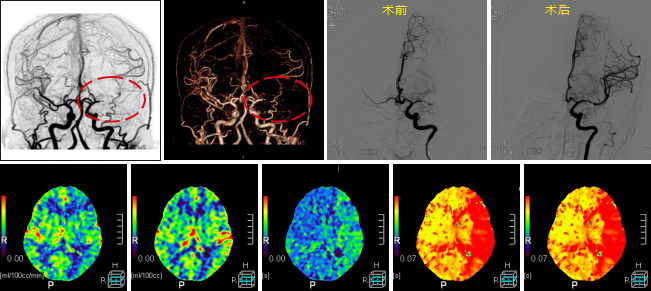

病例一 男,53歲, 突發(fā)右側(cè)肢體力弱, 言語(yǔ)不清, 伴惡心嘔吐、 伴頭暈頭昏、 伴視力模糊, 無(wú) 意識(shí)障礙、 無(wú)面癱。

CBT CBV MTT DLY TTP

從圖中CTA可見(jiàn)左側(cè)大腦中動(dòng)脈M 1段閉塞。

腦灌注所示左側(cè)大腦中動(dòng)脈供血區(qū)DLY、 TTP、 MTT時(shí)間顯著延長(zhǎng),CBF略減低, 考慮為 急性腦梗死; 左側(cè)額葉、 頂枕葉CBF、 CBV顯著減低, 符合軟化灶表現(xiàn)。

經(jīng)大動(dòng)脈腦血管造影+機(jī)械血栓清除+動(dòng)脈內(nèi)溶栓術(shù), 顯示血管病變位置與CTA顯示病變 位置相符, 治療后, 該血管供血區(qū)域得到明顯改善。

核磁共振檢查證實(shí)梗死核心區(qū)域與灌注圖所示區(qū)域匹配。

640層寬體探測(cè)器CT為16 cm覆蓋不動(dòng)床一站式神經(jīng)成像, 通過(guò)一次注藥, 一次掃描可以 獲得完整的純動(dòng)脈期、 純靜脈期和腦血流功能灌注成像及動(dòng)態(tài)CT- DSA電影圖像, 每一個(gè)動(dòng) 態(tài) 數(shù) 據(jù) 都 是 在 同 一 時(shí) 相 獲 得 , 同 時(shí) 包 含 了 解 剖 和 功 能 的 信 息 , 通 過(guò) 對(duì) 神 經(jīng) 一 站 式 的 快 速 分 析, 在60 秒內(nèi)就可以完成急性腦卒中的全面評(píng)估。

不動(dòng)床的采集模式避免了螺旋穿梭式灌注帶來(lái)的全器官不在同一時(shí)相采集、 連續(xù)曝光劑 量大的不足; 獨(dú)有的SVD+算法帶來(lái)精準(zhǔn)的灌注結(jié)果, 結(jié)合獨(dú)有的全顱冠狀位和矢狀位的灌 注圖及血管與灌注融合圖像可以清楚顯示梗塞血管及其造成的低灌注區(qū)域, 帶來(lái)精準(zhǔn)的檢查 結(jié)果。

此外, 機(jī)器同時(shí)搭載了雙空間多模型的AIDR 3 D迭代技術(shù), 使得神經(jīng)一站式檢查的劑量 僅需2 - 3 m Sv,造影劑用量?jī)H需40 ml,有效降低了檢查所需的輻射劑量和造影劑用量, 特別 適合需要多次復(fù)查的患者。